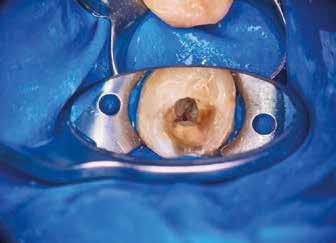

Helyi érzéstelenítést követően kofferdám került felhelyezésre, majd az izolálást folyékony kofferdám felvitelével (RUBBER-DAM liquid, CERKAMED) erősítettük meg (2. ábra). Ezt követően az ideiglenes tömést eltávolítottuk és a pulpakamrát desztillált víz, valamint ultrahangos hegyek segítségével aktivált 5,25%-os NaOCl oldattal megtisztítottuk (3. ábra). Az első mesio-bukkális (MB1), a diszto bukkális (DB) és a palatinális (P) gyökércsatorna átjárható volt, ezért először egy C-PILOT tű (VDW) és egy elektromos apexlokátor (E-PEX, Eighteeth) segítségével ezekben a csatornákban a munkahossz meghatározásra került. Ezután a gyökércsatornákat nagyjából az eredeti munkahossz kétharmadáig

A hozzáférési nyílás a referálást végző fogorvoskolléga által már előzetesen kialakításra került. A fogbélkamra inspekciója során visszamaradt pulpaszövetet észleltünk (22. ábra) A gyökércsatorna-bemenetek pontos lokalizációja előtt ezt még feltétlenül el kellett távolítani. Ez bármely endodonciai kezelés esetében érvényes, és a standard protokollunk része, mivel ellenkező esetben a pulpakamrában lévő törmeléket a gyökércsatornák mélyére juttathatjuk. Ehhez egy 2,780 nm-es hullámhosszon alkalmazott RFPT5–10 végződéssel ellátott (23. ábra) Er,Cr:YSGG lézer készüléket (Waterlase, BIOLASE) használtunk. A protokoll szerint ezen beavatkozás során először 1 percen keresztül folyamatos aktivációt végzünk, majd 1 percen keresztül nyugalomban hagyjuk a pulpakamrában lévő folyadékot (24. ábra). Csupán a fogbélkamrában lévő szövetek maradéktalan eltávolítását követően kezdhetjük meg a gyökércsatornák mechanikai feltágítását. A fogbélkamra megtisztítását követően (25–26. ábra) egy forgómozgást végző gépi gyökértágítót használtunk a gyökércsatorna megmunkálására. Ez ebben az esetben egy 12.5/.04 R-PILOT (VDW) gépi tű volt (27. ábra). A gyökércsatorna-rendszer belső anatómiai felépítésére és a szűk gyökércsatornákra való tekintettel hoztuk meg azt a döntést, hogy kizárólag ezt az egy tűt használjuk a mechanikai megmunkálás során. A feltágítás során a ki-be (in-out) technikát alkalmaztuk. Az egyes tágítási fázisok között nagy volumenű átöblítést és lézeres aktiválást végeztünk. A végső átöblítés során az aktiválást egy RFPT5–10 végződéssel ellátott Er,Cr:YSGG lézerrel végeztük (28–29. ábra).